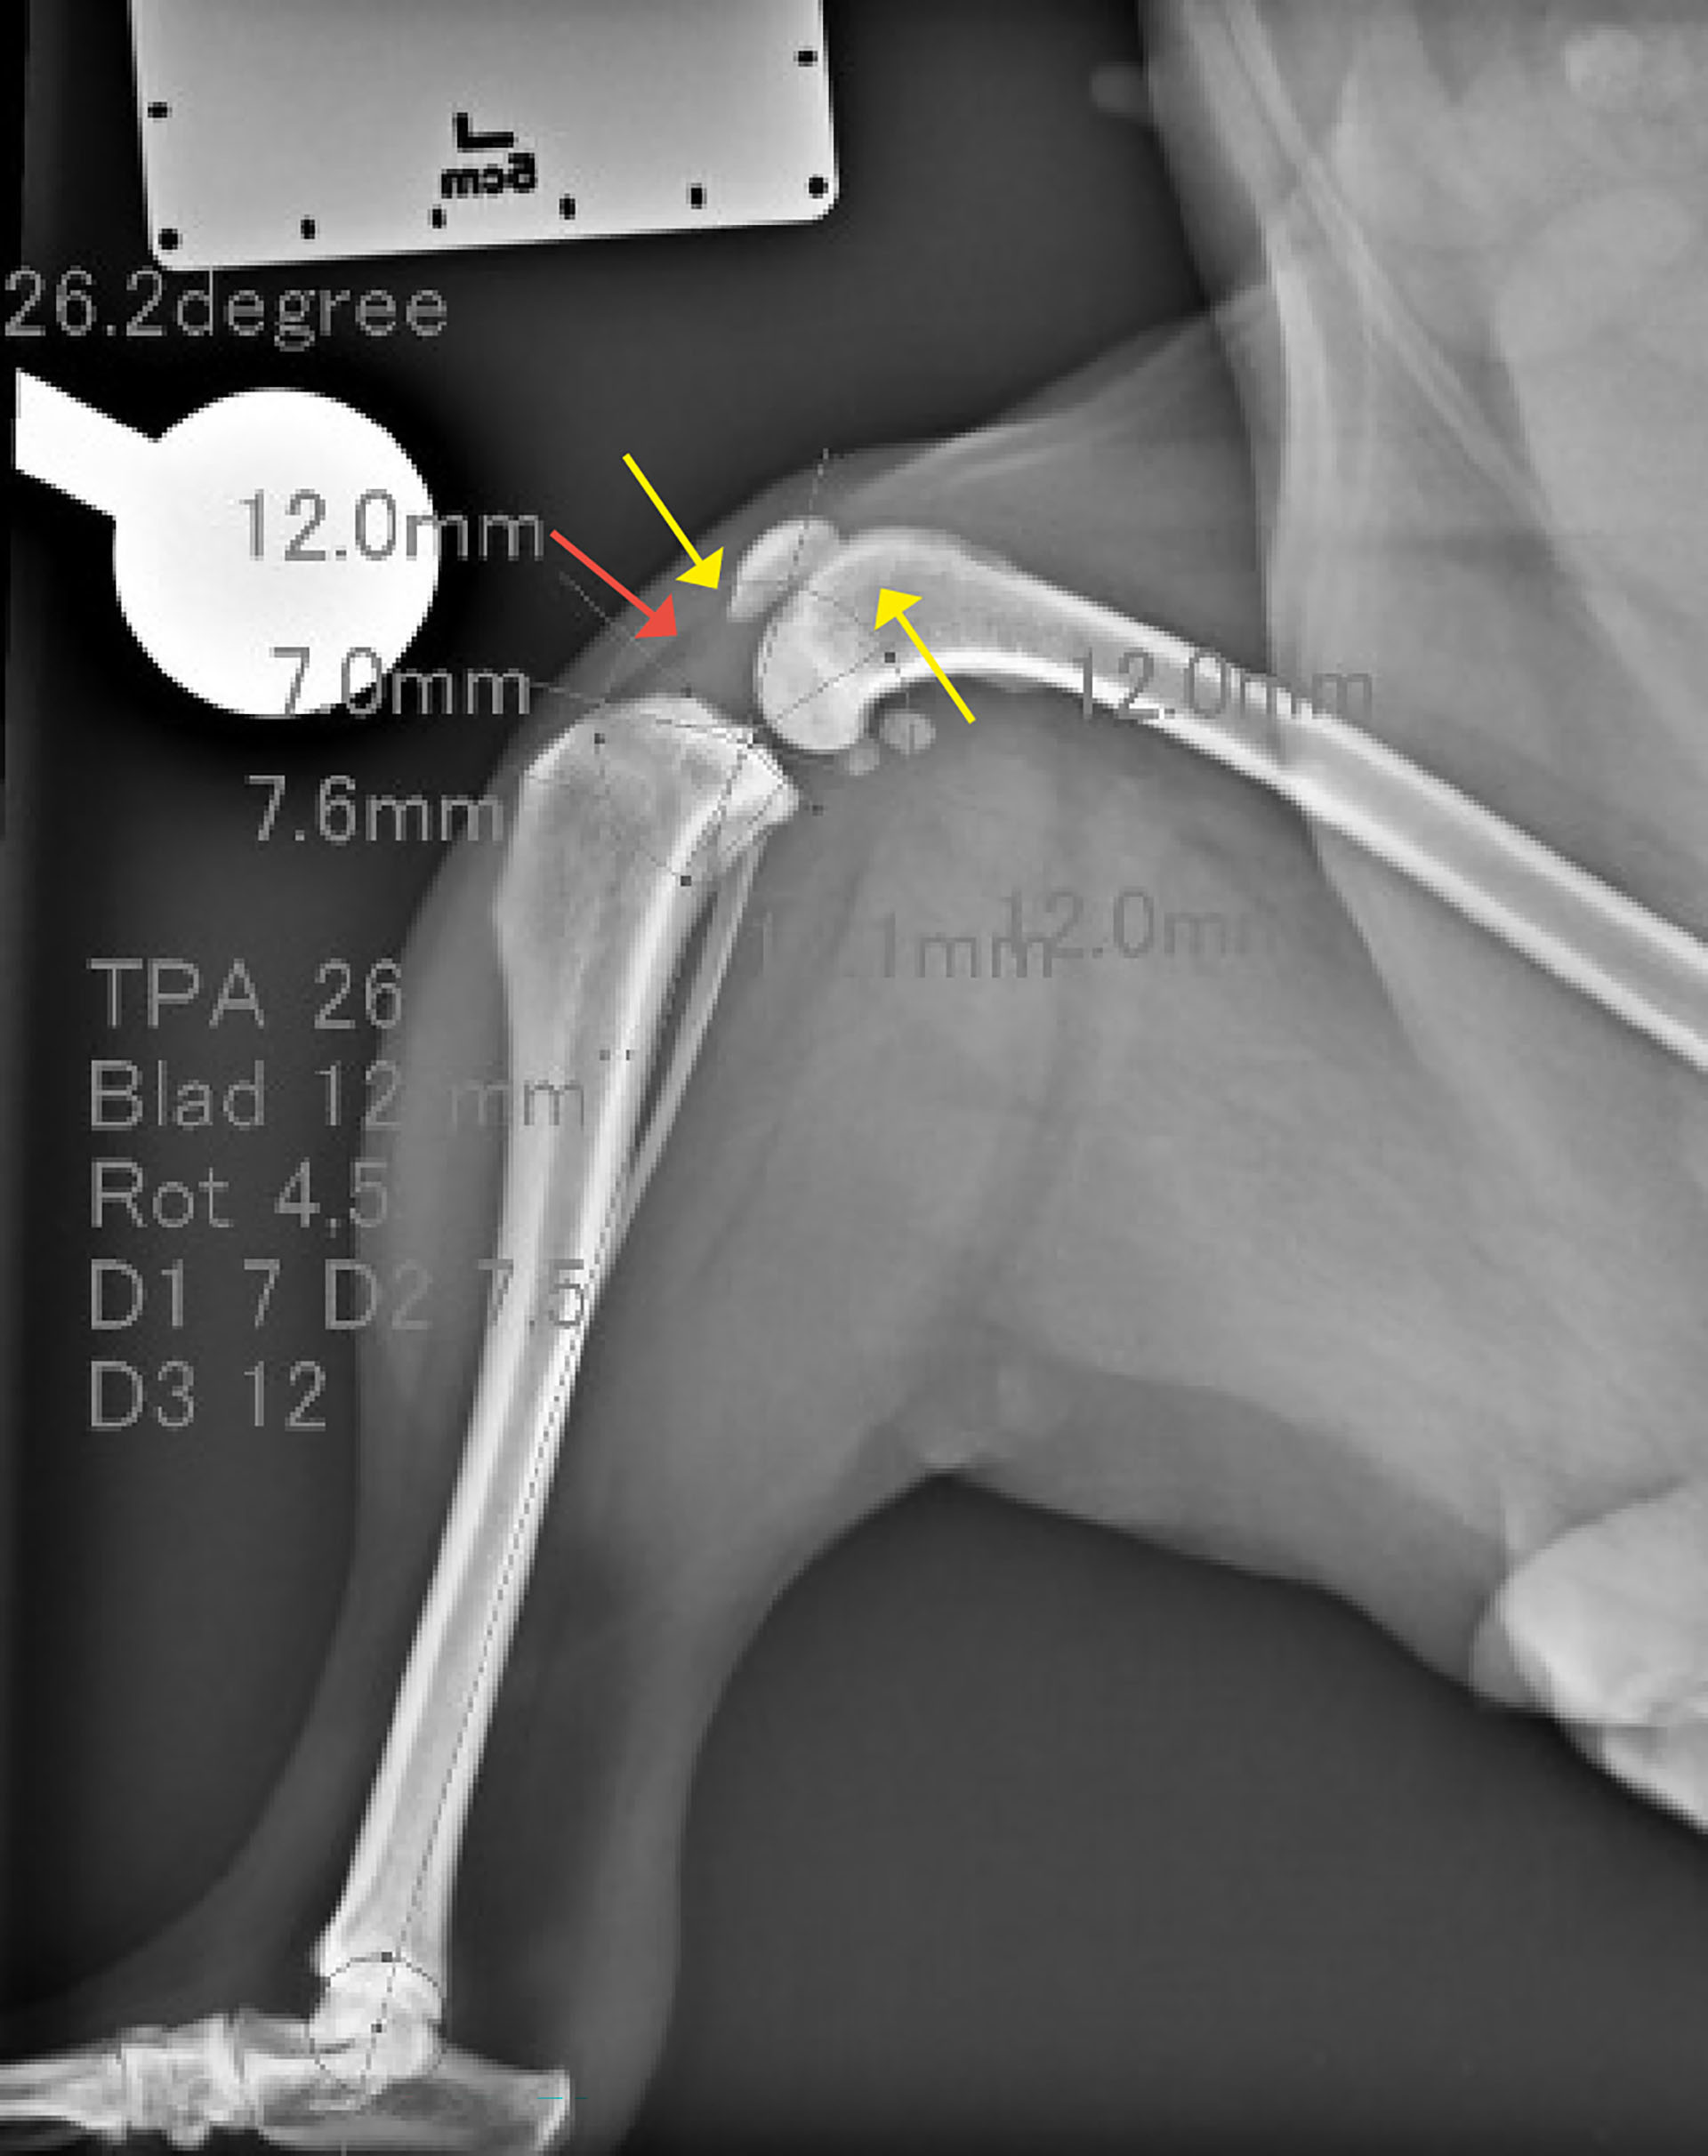

Figur 1. Laterolateral projeksjon av venstre kne og haseledd. I venstre kneledd var det tydelig effusjon (rød pil), og osteofyttdannelse på patellas apex og femoral ridge (gule piler).

Laterolateral projeksjon og kraniokaudal projeksjon av hundens høyre og venstre kneledd, tibia, fibula og tarsalledd var tilgjengelig for vurdering. Kvaliteten på bildene var akseptabel. Det ble funnet tydelig effusjon i venstre kneledd med et brattere tibiaplatå enn ved høyre kne. Venstre kne hadde tegn på osteofyttdannelse på apex patella og femoral ridge som tydet på tidlig osteoartoseforandringer. Tibiaplatå vinkelen (TPA) ble målt til 26,2 grader. Denne vinkelen måles mellom en perpendikulær linje til lengdeaksen av tibia og en linje parallell til tibiaplatået. En større tibiaplatåvinkel resulterer i større kranial kraft av tibia under vektbæring. Det kunne ikke påvises annen patologi utifra disse bildene.